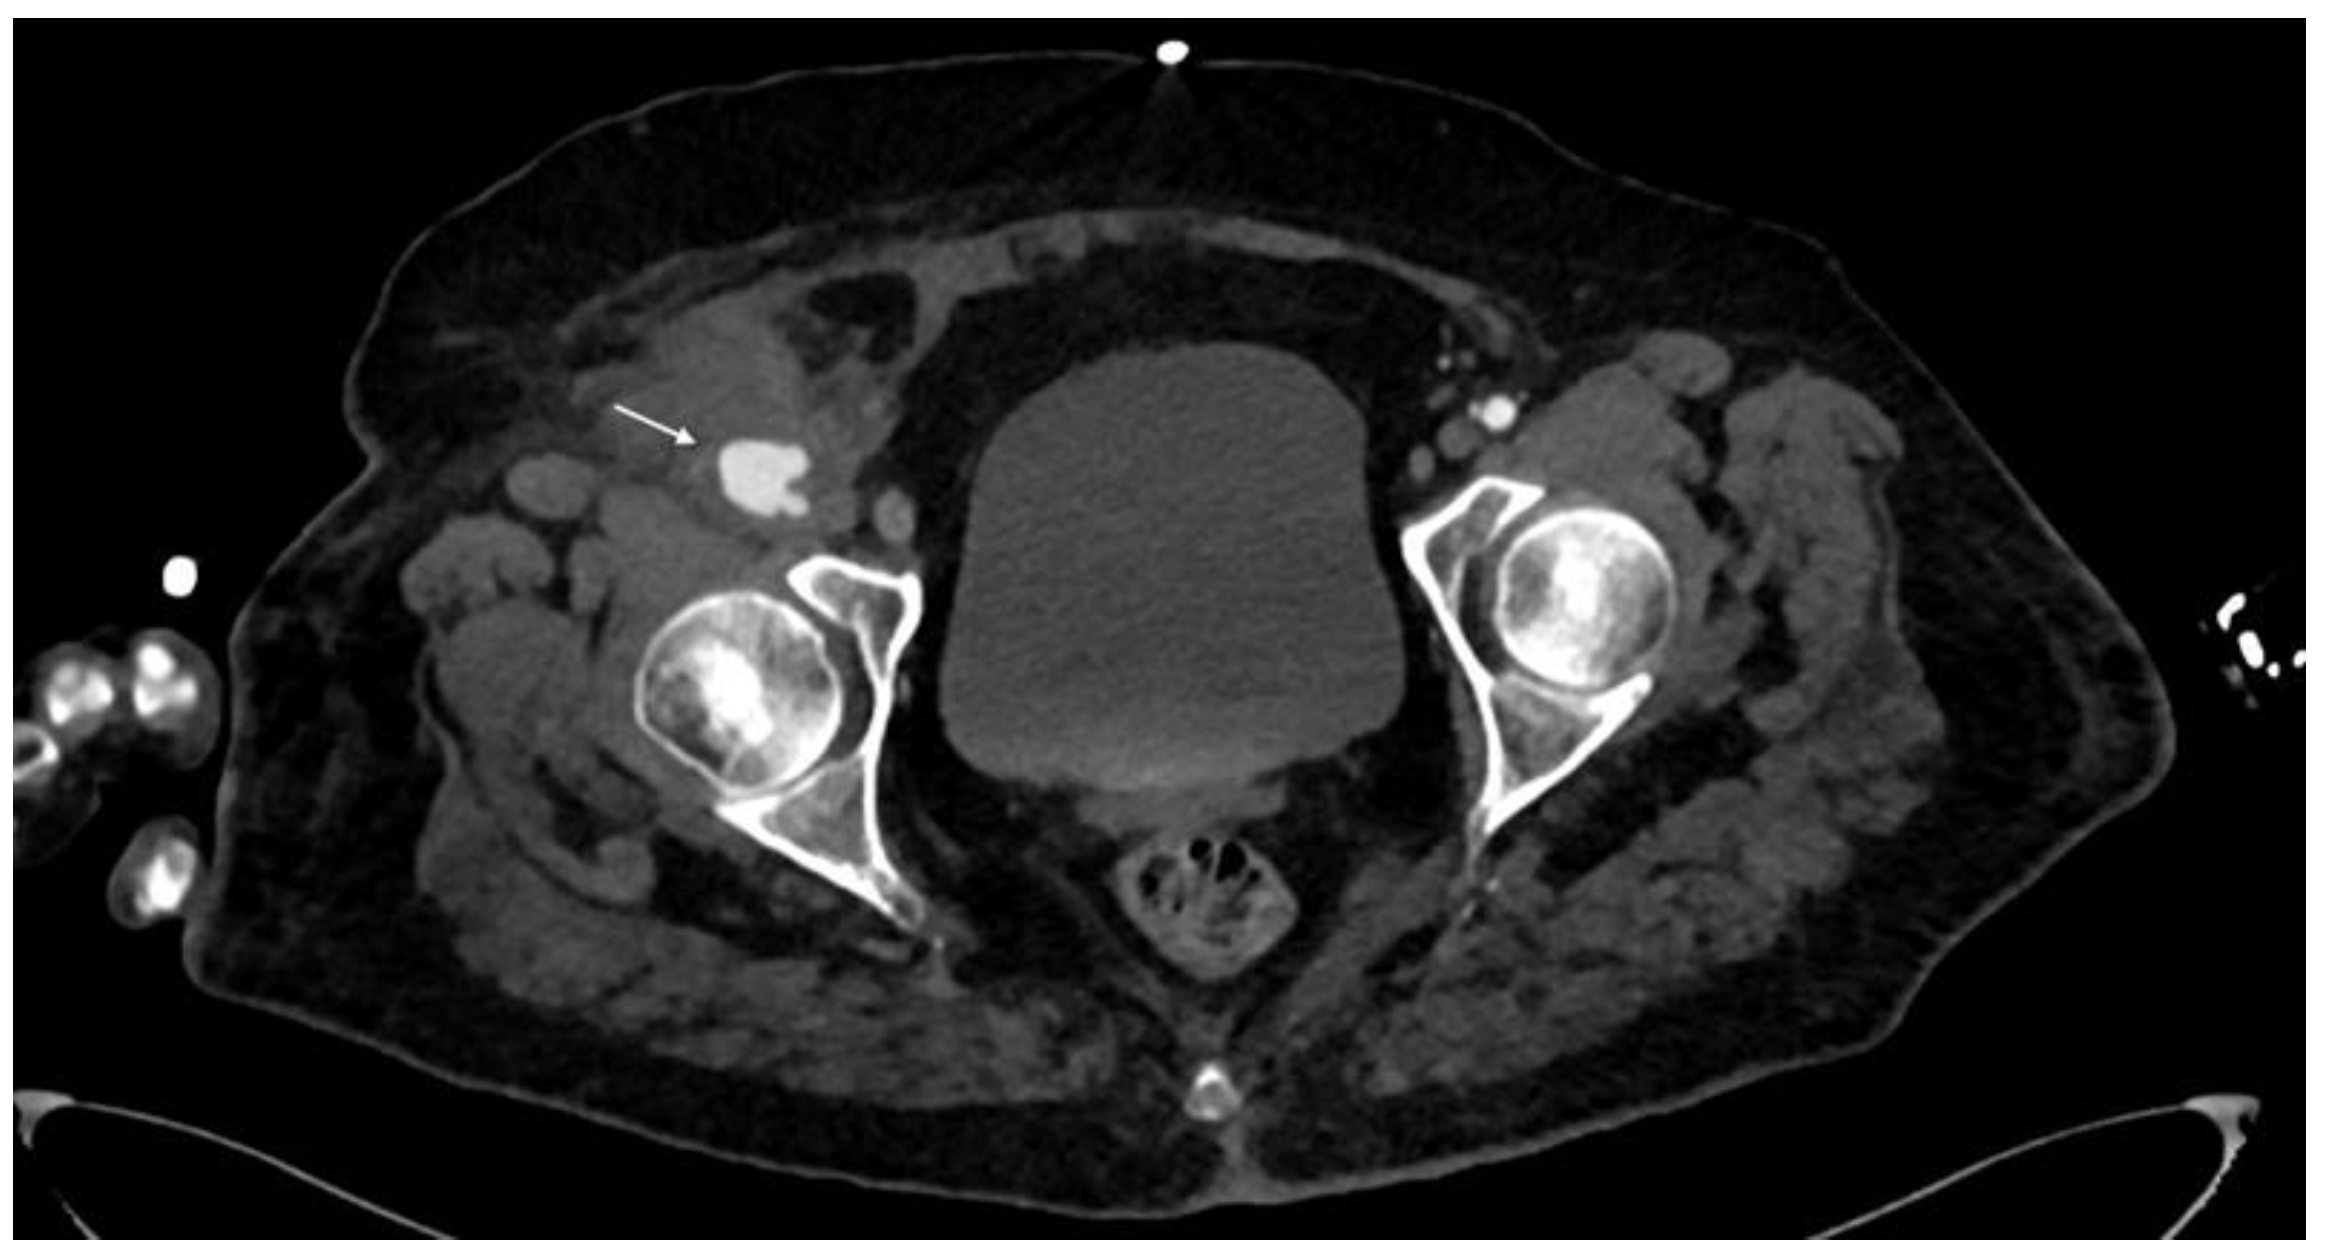

3.2. CTA Imaging Findings